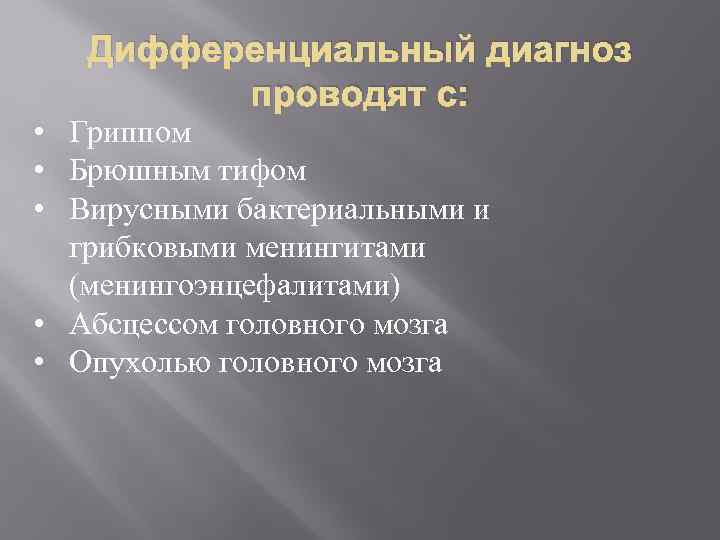

Дифференциальный диагноз проводят с: • Гриппом • Брюшным тифом • Вирусными бактериальными и грибковыми менингитами (менингоэнцефалитами) • Абсцессом головного мозга • Опухолью головного мозга

Дифференциальный диагноз проводят с: • Гриппом • Брюшным тифом • Вирусными бактериальными и грибковыми менингитами (менингоэнцефалитами) • Абсцессом головного мозга • Опухолью головного мозга